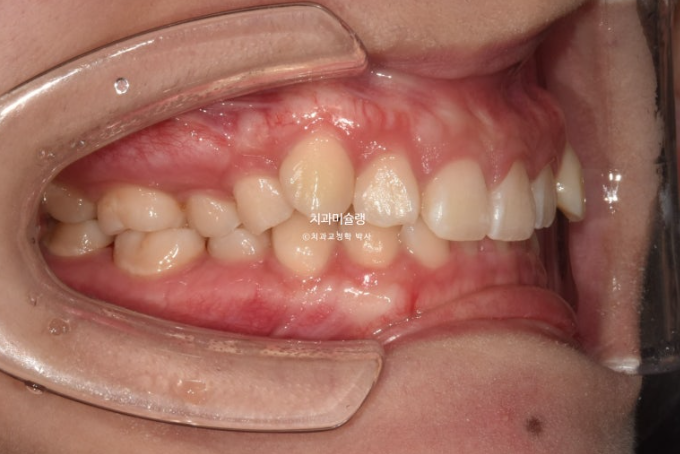

중심선이 약 2mm 어긋나 있으며 송곳니 덧니가 보입니다.

위 아래 앞니가 깊게 물리는 과개교합도 보입니다.

웃을때 잇몸이 많이 보이는 거미스마일이 있습니다. 특히 위 앞니가 뒤로 쓰러진 옥니 입니다.

작은어금니 하나가 매복되었다시피 깊게 누워있습니다.

치료계획은 누워있는 덧니를 포함해서 작은어금니 4개 발치

단 입이 너무 들어가는 것은 원치 않아 모르페우스 시뮬레이션을 통해 앞니 들어가는 양을 2mm정도로 제한하기로 합니다.